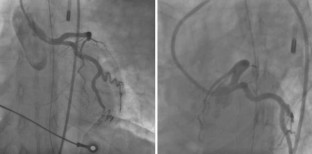

A 35-year-old woman was admitted to our hospital because of a sudden cardiac arrest caused by an acute anterior myocardial infarction. Emergency coronary angiography showed total occlusion of the proximal left anterior descending artery (LAD). We performed an intravascular ultrasound (IVUS) to detect the LAD orifice and successfully inserted the guidewire to the occluded LAD. An IVUS revealed coronary dissection and no atheromatous plaque from the orifice to the mid-portion of the LAD and the guidewire was in the true lumen. Two bare metal stents were implanted in the proximal and mid portion of the LAD. After stenting to the LAD, coronary dissection retrogradely extended to the left circumflex artery (LCx). Therefore, we performed additional stent implantation from the left main trunk (LMT) to the proximal LCx and the just proximal LAD. An IVUS guided percutaneous coronary intervention (PCI) enabled complete revascularization to spontaneous coronary artery dissection.

Fig. 2

Fig. 3